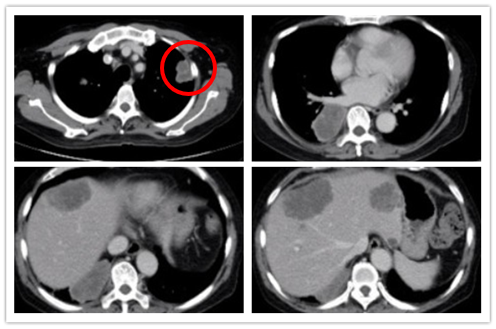

2019-2中旬CT评估:

2019-2中旬CT评估

2019-3下旬CT评估

2019-5下旬CT评估

CT评估(肺部病灶)